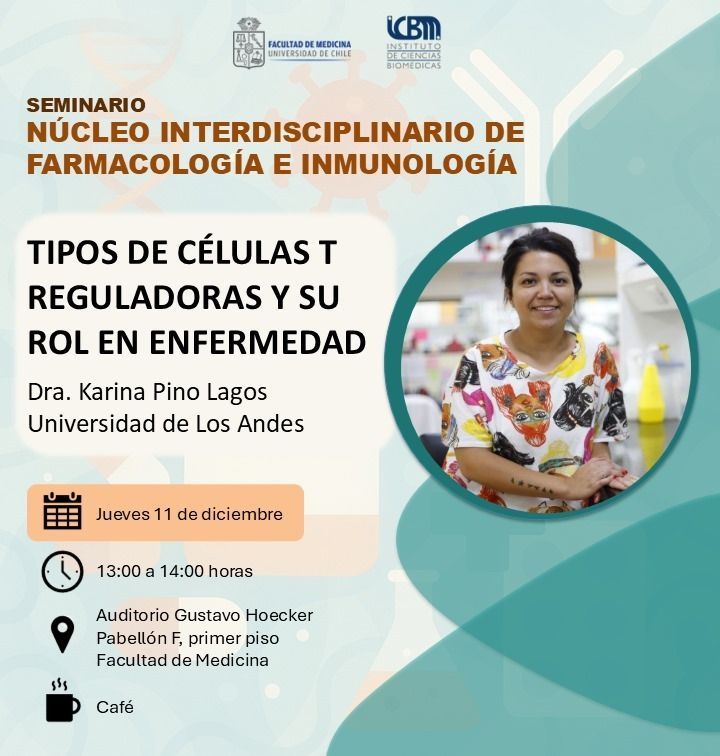

Las primeras jornadas de investigación y docencia en farmacología e inmunología fueron todo un éxito! Muchas gracias a todos los que participaron, en especial a nuestros expositores 👏👏👏👏 ICBM Concha Peiró Facultad de Medicina